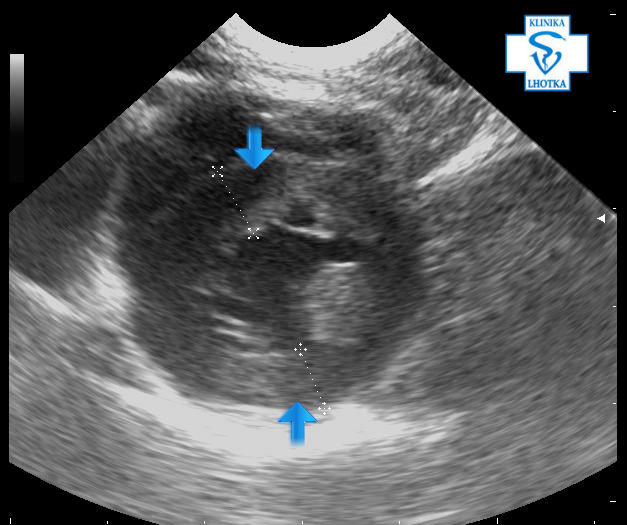

Stejné struktury jsou zobrazené v příčném zobrazení srdce a to v systole (při staženém srdci):

Echokardiografie-HCM-krátká osa-systola

A diastole (při roztaženém srdci):

Echokardiografie-HCM-krátká osa-diastola